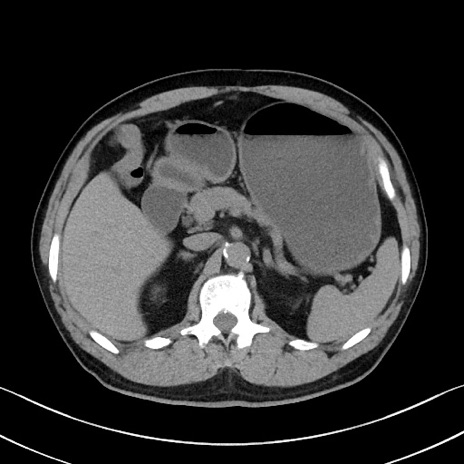

症例35(横断像)

【症例】70歳代 男性

【主訴】腹部膨満、嘔吐

【現病歴】昨日より腹部膨満感出現。本日増悪し、仙痛出現。嘔吐あり、受診。

【既往歴】糖尿病、胆摘後

【身体所見】BP 149/80mmHg、HR 74/min、BT 35.9℃、腹部:膨満、軟、圧痛なし。腸雑音減弱あり。上腹部正中切開瘢痕あり。

【データ】WBC 13500、CRP 1.72